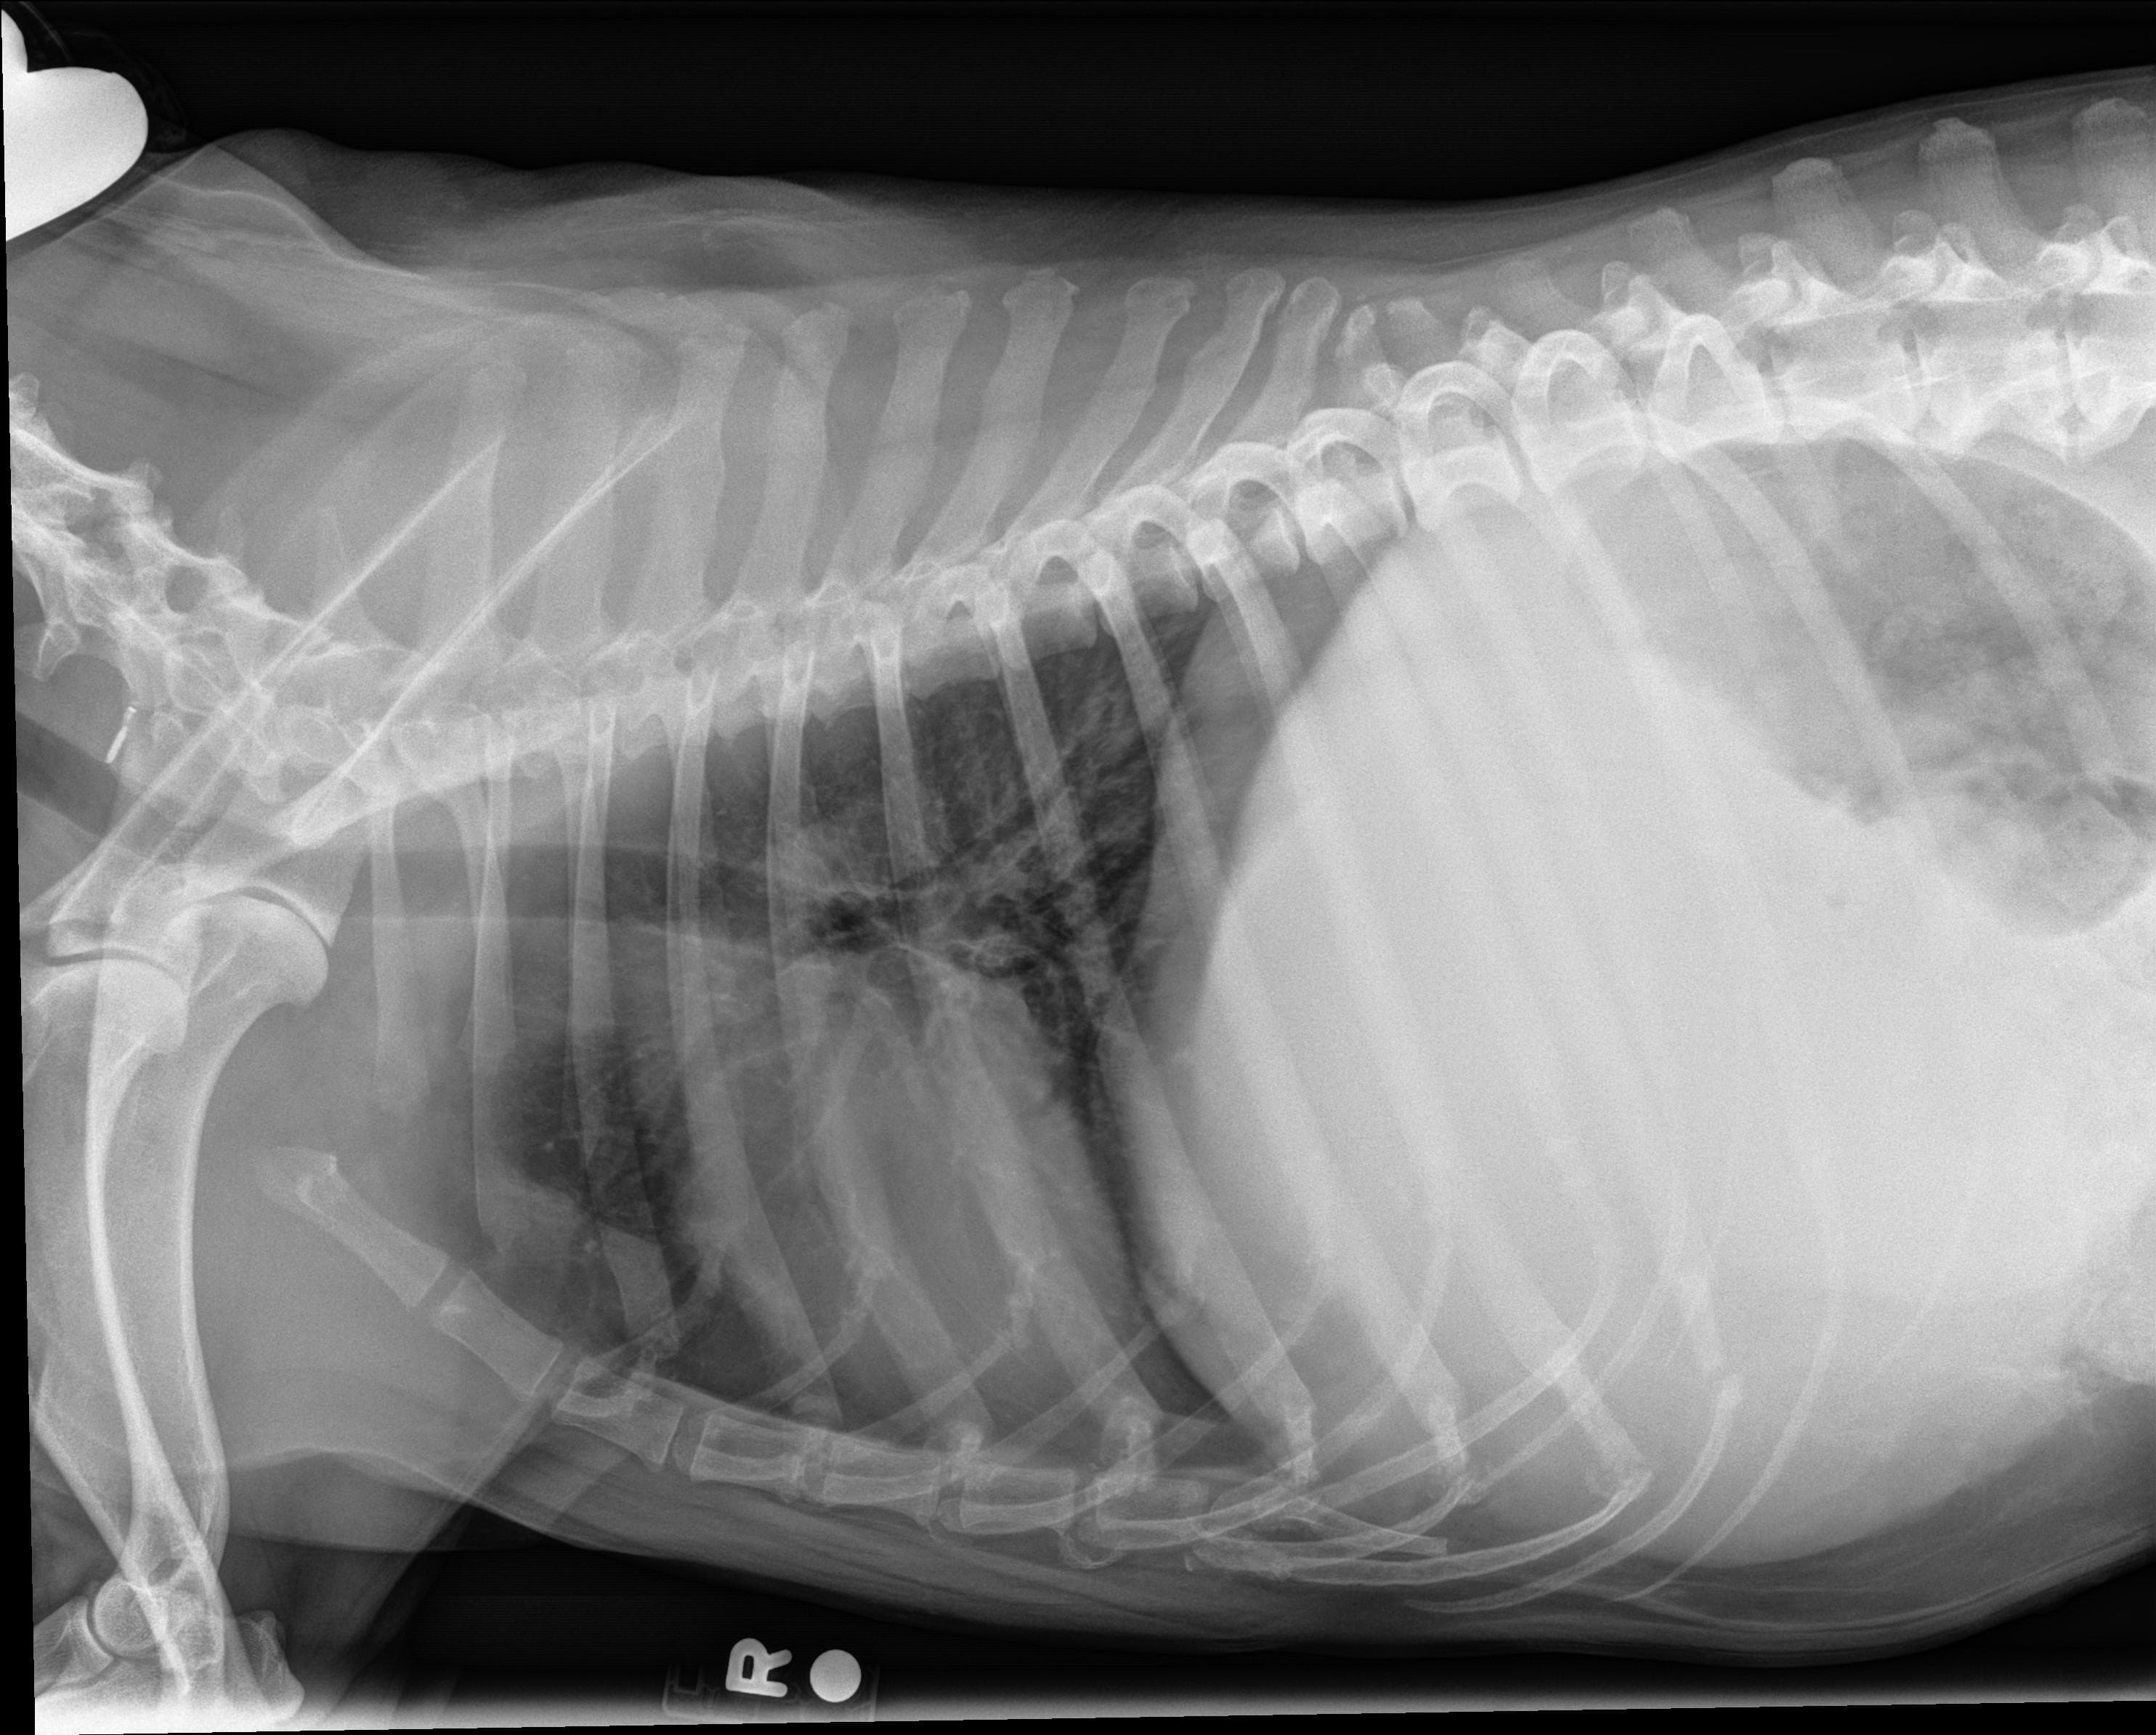

Jello. I have a 12 yr old dog. She has a high fever, dehydration, not eating, etc. She lost over 5 lbs in a short while. Our vet took xrays and said her liver is very enlarged, packed with tumors and pressing on her stomach and lungs. Im attaching the xrays and would appreciate your thoughts. Thank you

Poor amber,, that liver is massively enlarged and I would expect breathing difficulties, inability to eat and abdominal pain. Although scans and biopsies may provide information on the underlying cause, euthanasia may be the kindest option at this stage